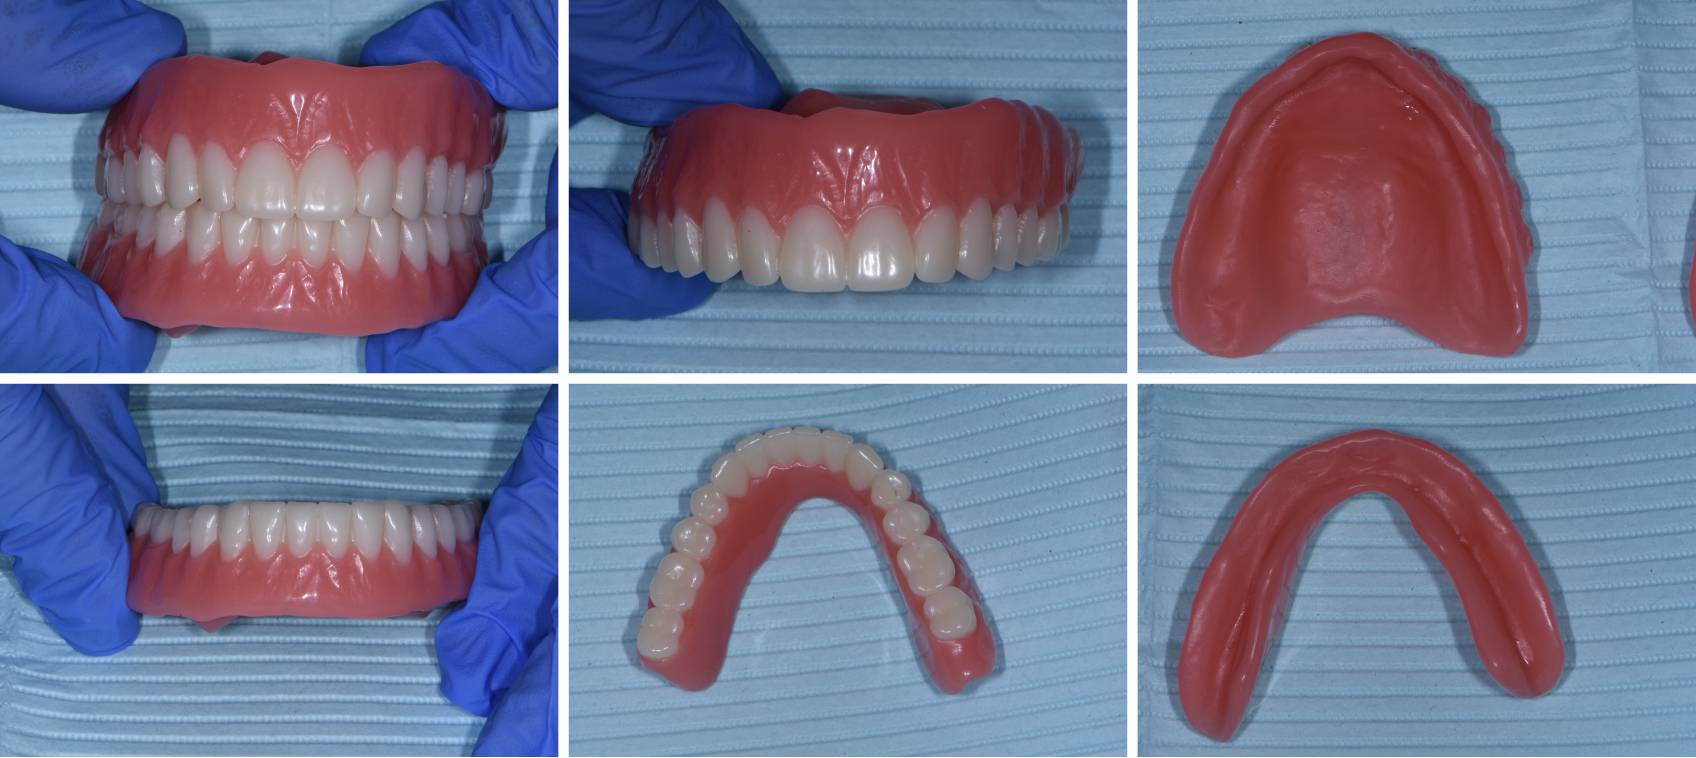

In this case, everything was spot-on, except I had missed a small area on the intaglio of one of the old dentures when I did the 360-degree scan of the wash impression. This was easily rectified, however, by simply doing a second wash impression using this try-in and sending it to the lab to be scanned with their desktop scanner. (This has its own advantages because, in situations like this, desktop scanners are less prone than intraoral handheld scanners to introduce errors.) The final dentures (Figs. 22–27) were then fabricated.

The patient and I were both blown away by these new dentures, which required zero adjustment. She might have been even more impressed than I was — remember, she had worked in the lab that made her previous set of dentures, so she found it hard to believe how smoothly everything had gone and how few steps there were, compared with the old-school analog workflow.

From start to finish, only three visits were required:

- The initial records appointment, which included 360-degree scans of the denture after a wash impression, a scan of the bite with the dentures in the patient’s mouth, and photographs of the existing dentures in the patient’s face, so we could plan the esthetics and tooth position of the new dentures.

- The try-in of a printed mock-up.

- Delivery of the final denture.

I had planned to take final photos with dentures in the patient’s mouth at a follow-up adjustment appointment, which you typically have multiple of, but the patient never needed any.